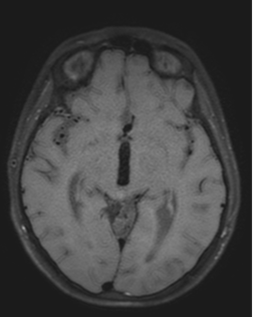

Dos años más tarde, en control por Infectología, refirió cefalea holocraneana pulsátil de moderada intensidad, asociada a mareos, náuseas y vómitos esporádicos. Se solicitó una nueva angioRM, la que arrojó un aneurisma fusiforme de la arteria comunicante anterior con compromiso del segmento A2 izquierdo e irregularidad asociada de M1 derecho (Figuras 3 y 4). Ante estos hallazgos se efectuó angiografía cerebral con colocación de un diversor de flujo, angioplastia con balón y embolización con “coils”.

Figura 4. Angiografía digital cerebral, reconstrucción 3D: se observa dominancia de la ACA derecha con pasaje a través de la ACoA hacia la ACA izquierda. A nivel de la ACoA se identifica un aneurisma fusiforme que compromete toda su longitud y se extiende hasta el extremo proximal del segmento A2 izquierdo. Del domo aneurismático emerge una rama arterial.